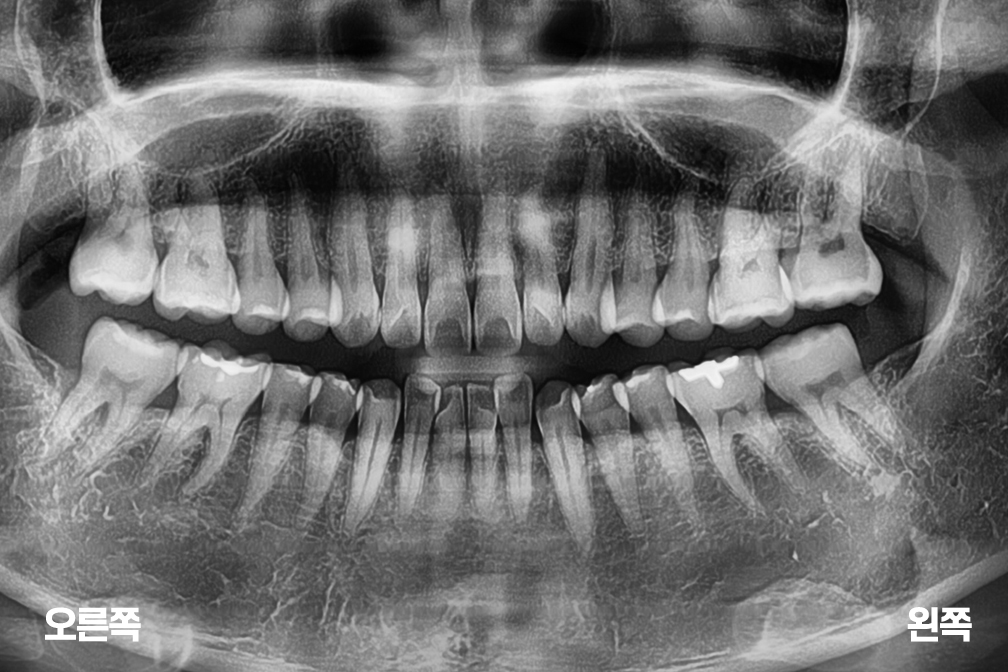

Before 2025년 8월 19일